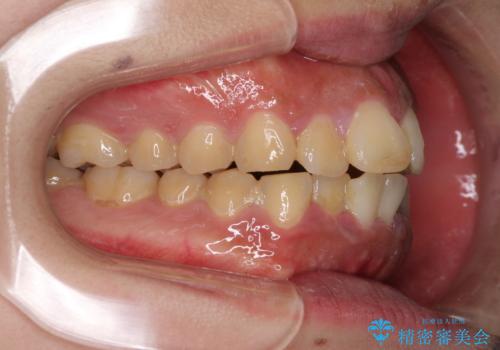

- 口元の突出感と上下前歯のでこぼこを気にして来院された患者様です。

上下前歯部叢生のスペース獲得のため、上下顎左右小臼歯各1歯(計4本)を抜歯して、矯正治療を行うこととしました。